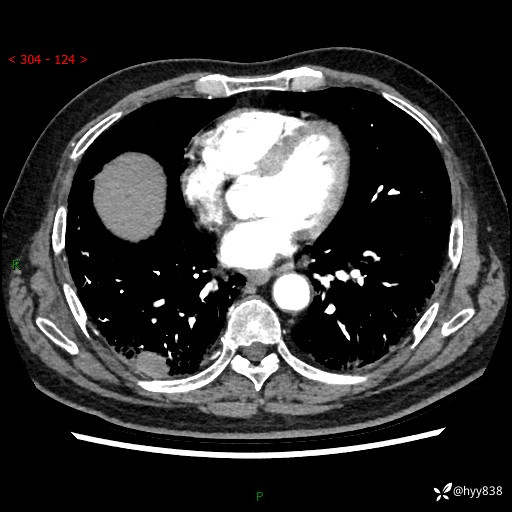

71岁/男,咳嗽伴气促半月。一年前肺手术史,又见两个结节,穿刺结果意外---结果公布~

【患者信息】:71岁/男

【主诉】:咳嗽、咳痰伴气促半月

【现病史】:患者半月前无明显诱因出现咳嗽、咳痰,为白色粘痰,无明显加重与缓解因素,伴气促,无发热,无大量脓痰,无胸痛、咯血,无哮鸣音,到我院就诊,胸部CT示右肺结节增大,并口服药物治疗无明显好转,具体用药不详,为求进一步治疗随来我院,经门诊以“孤立性肺结节”收入我科。 病程中患者精神、饮食可,睡眠不佳,大小便正常,体力下降,体重未见明显下降。

[既往史]:2022-06于当地第一人民医院确诊慢阻肺,现规律使用杰润(1次/日);2023-04-06于当地市第一人民医院行胸腔镜右肺上叶楔形切除术+右肺上叶切除术+淋巴结清扫术+胸膜黏连松解术,确诊为右肺鳞癌 pT2aN0M0 Ib期

【检查】:胸部CT平扫+增强